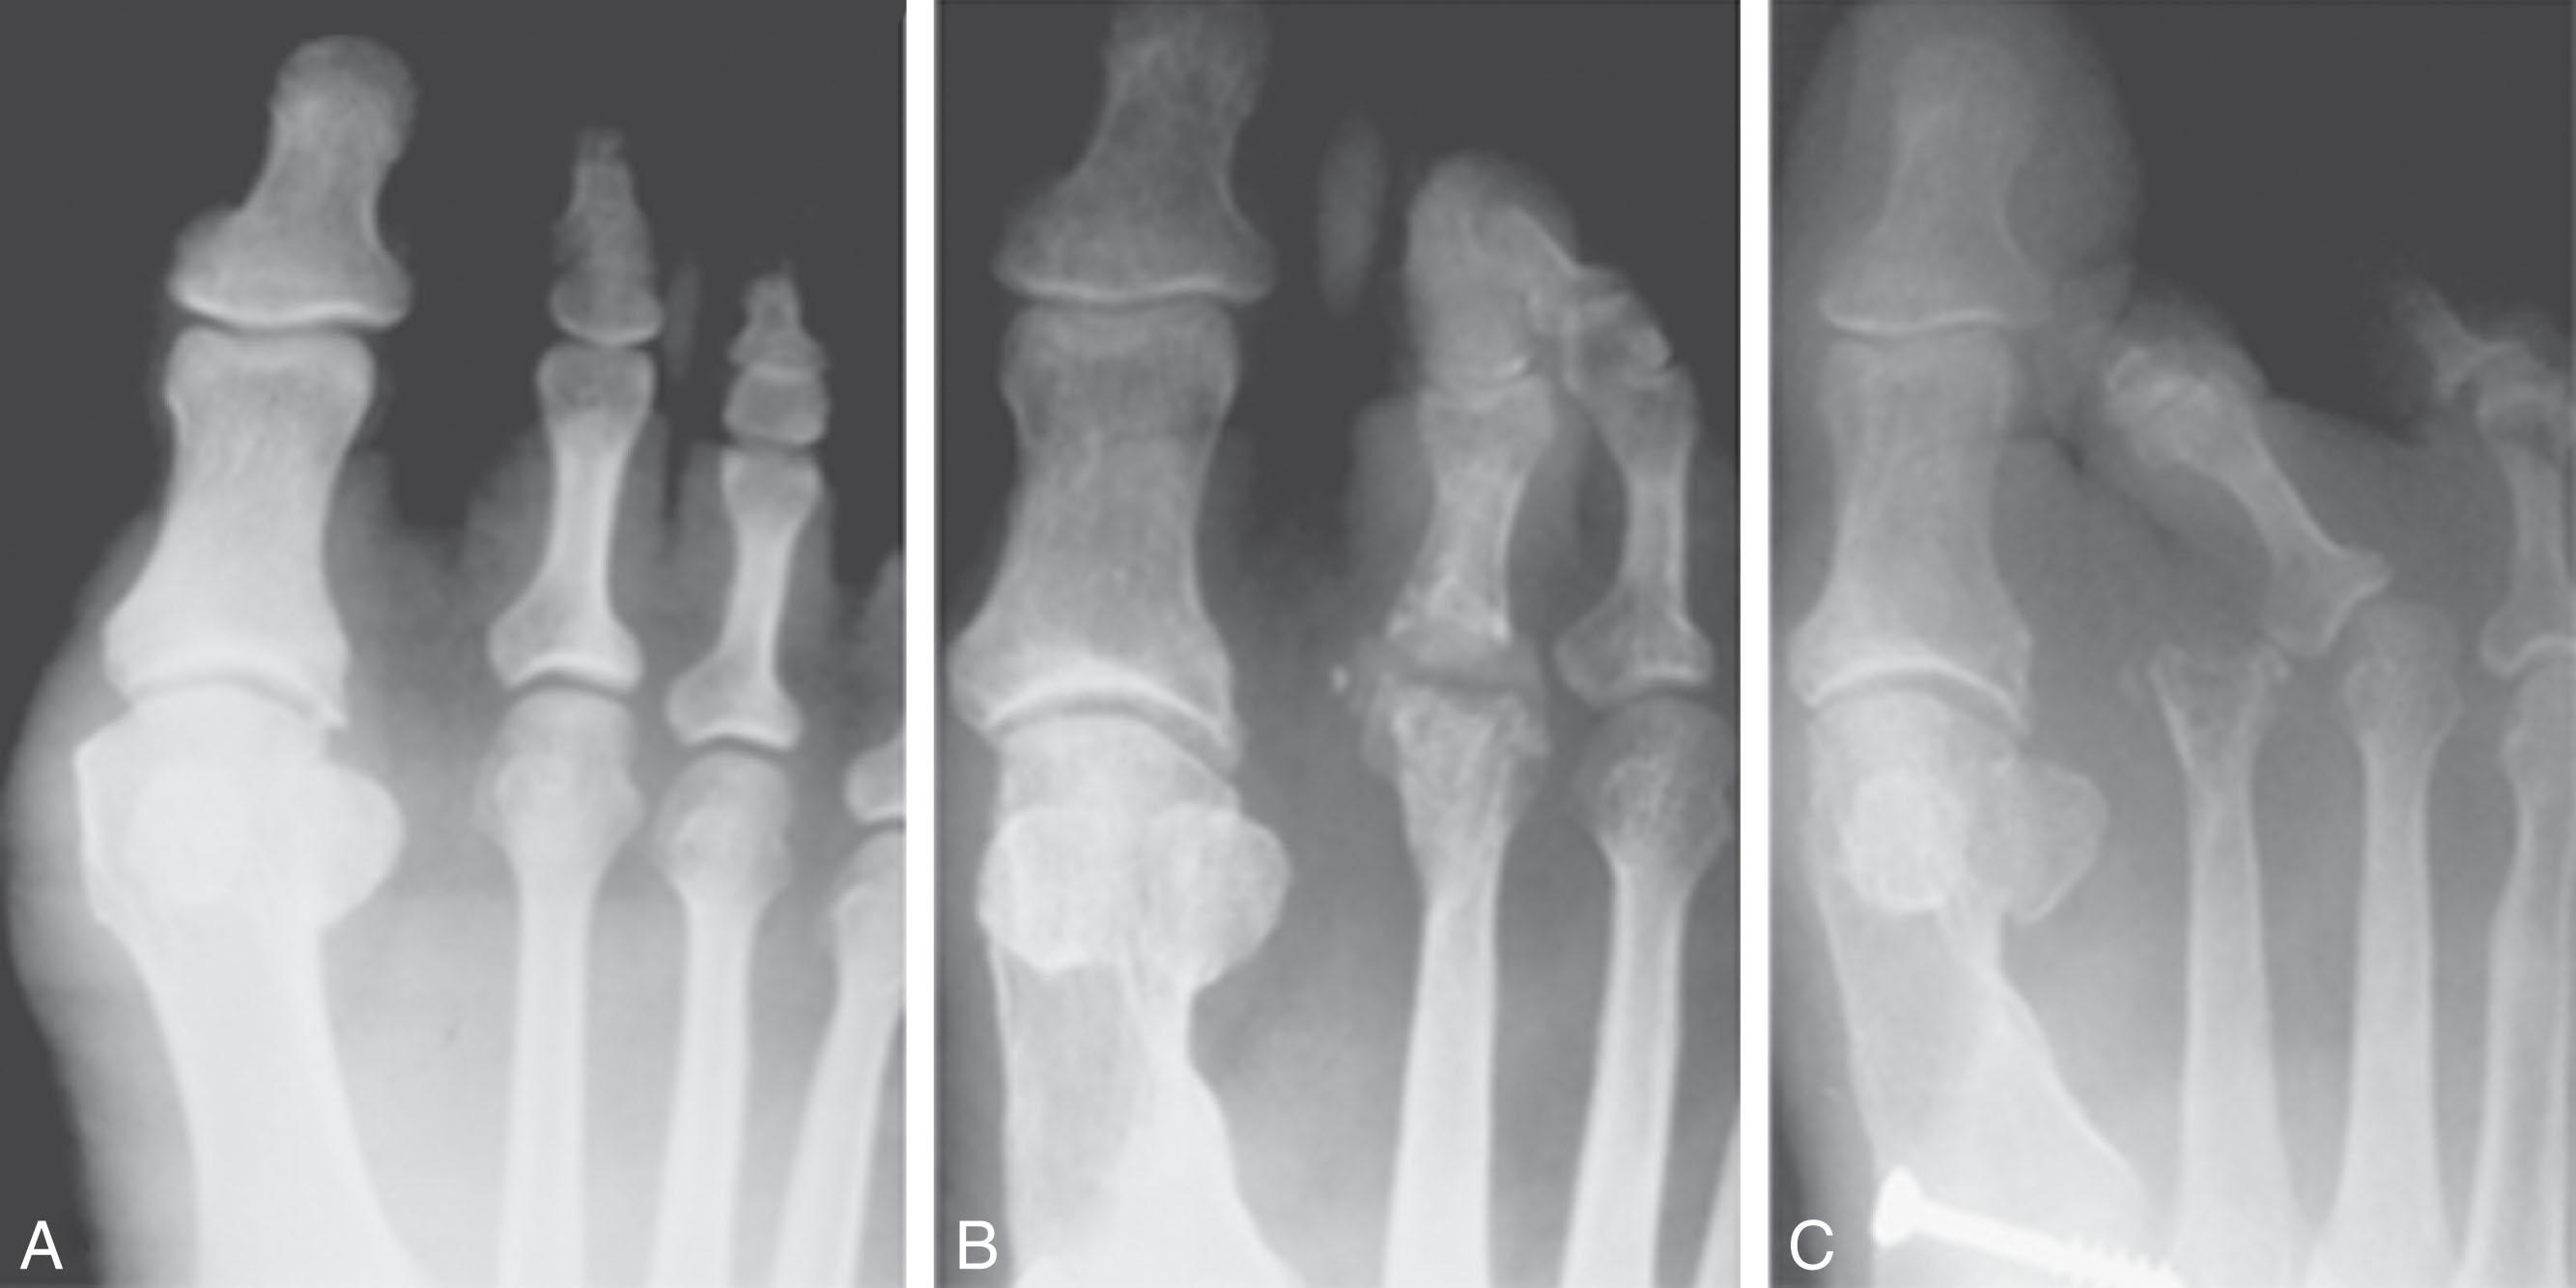

Although a physical examination is necessary to define the extent of a lesser toe deformity, radiographic examination is necessary to evaluate the magnitude of the bone deformity ( Fig. 9-30B ). On an anteroposterior (AP) projection, a severe hammer toe deformity can have the appearance of a gun barrel deformity ( Fig. 9-30C ) when the proximal phalanx is seen end on. Assessment of the interphalangeal joints is difficult on this projection. Diminution of the MTP joint space can indicate subluxation, and overlap of the base of the proximal phalanx in relation to the metatarsal head can indicate dislocation of the MTP joint ( Fig. 9-31 ). Medial or lateral deviation of the MTP joint can be determined as well. Subchondral erosion, flattening of the articular surfaces, or a Freiberg infraction can indicate the need for further radiographic or laboratory evaluation.

Fig. 9-31, A , A 52-year-old man with pain at the second metatarsophalangeal (MTP) joint and a slight hallux valgus deformity. B , Six-month follow-up demonstrates narrowing of the joint space, pathognomonic of a hyperextension deformity. Often subluxation can occur insidiously. C , At 15-month follow-up, the second MTP joint has dislocated.